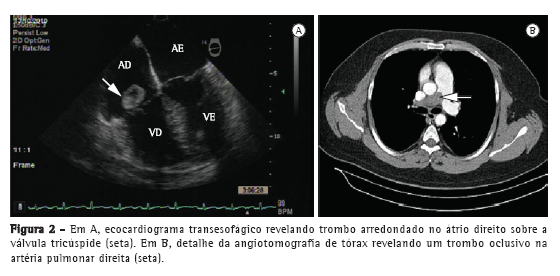

Homem de 37 anos deu entrada no setor de emergência do Hospital das Clínicas da Universidade Federal de Minas Gerais (HC-UFMG), localizado na cidade de Belo Horizonte (MG), com dispneia moderada há dois dias. O paciente apresentara um episódio semelhante há dois anos, que fora tratado como broncoespasmo. Como antecedentes, o paciente fora submetido à amputação transtibial do membro inferior esquerdo há seis anos devido à oclusão de artéria poplítea. Após anticoagulação (varfarina) por um ano, teve diagnóstico de compressão muscular da artéria poplítea direita, corrigida cirurgicamente. Naquela ocasião, detectou-se elevação do fator VIII (200 UI/dL) em uma amostra. O paciente apresentava eletrocardiograma normal. Ao exame, estava alerta, com SpO2 de 90%, FC de 72 bpm e pressão arterial de 150/100 mmHg. O exame cardiopulmonar estava normal. A radiografia de tórax evidenciava acentuação das marcas vasculares à esquerda. O ecocardiograma transtorácico (ETT) revelava trombo móvel aderido ao folheto posterior da válvula tricúspide (18 × 15 mm) insinuando-se para o ventrículo direito (VD). Outro trombo (13 × 14 mm) estava localizado na veia cava inferior (VCI), havendo hipocontratilidade difusa no VD e relaxamento diastólico anormal no ventrículo esquerdo. A cintilografia pulmonar (CP) revelava padrão homogêneo à inalação e perfusão com distribuição acentuadamente diminuída à direita e homogênea à esquerda (Figura 1). Embora o paciente tivesse recebido anticoagulação, evoluiu com persistência da dispneia e SpO2 de 93%. O ecocardiograma transesofágico (ETE) revelava grande trombo móvel no átrio direito (AD), projetando-se para o VD e disfunção do mesmo (Figura 2A). A angiotomografia de tórax revelava consolidações periféricas à direita, artéria pulmonar direita (2,9 cm) ocluída e defeito de enchimento dos ramos lobares superior, médio e inferior e dos ramos segmentares e subsegmentares, além da presença de trombos em seis ramos subsegmentares do lobo inferior esquerdo (Figura 2B). O ETT de controle, realizado 17 dias após, revelava fração de ejeção de 0,79, VD dilatado e hipocinético, pressão sistólica da artéria pulmonar de 39 mmHg e persistência do trombo em AD. Nessa fase, manteve-se a anticoagulação oral, segundo decisão conjunta com o paciente e seus familiares. O paciente recebeu alta em uso de varfarina com encaminhamento para a pneumologia. Devido à piora da dispneia, o paciente foi readmitido no mês seguinte. A CP apresentava padrão semelhante ao anterior. O ETT revelava persistência dos trombos intra-atrial e da VCI, embora menores em relação ao exame anterior. Diante dessas alterações e dos sintomas, realizou-se trombólise (alteplase, 100 mg em 2 h) em regime de UTI, que transcorreu sem complicações. O ETE realizado cinco dias após a trombólise mostrava o desaparecimento completo do trombo do AD, persistindo o trombo em VCI (17 mm). A CP de controle 72 h após não revelava sinais de reperfusão pulmonar. O paciente recebeu alta com a melhora da dispneia, em uso de varfarina, e foi referenciado para acompanhamento ambulatorial no Serviço de Pneumologia do HC-UFMG.